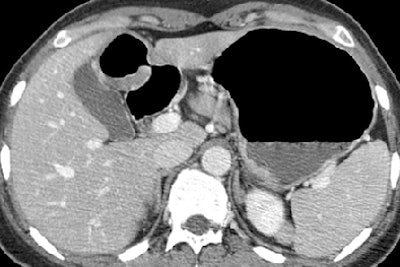

| Early gastric cancer in a 33-year-old woman. There is no identifiable gastric wall thickening on either the transverse CT scan (a, above) or the coronal MPR image (b, below). Virtual endoscopic image (c, bottom) shows a shallow depressed lesion with surrounding mucosal nodularity (arrows) in the angle of the stomach, suggesting early gastric cancer (T1). At histopathologic analysis, this lesion was diagnosed as type IIb + IIc early gastric cancer (pT1). Images used with permission of the Radiological Society of North America (Radiology 2005 Sep;236(3):879-85). |